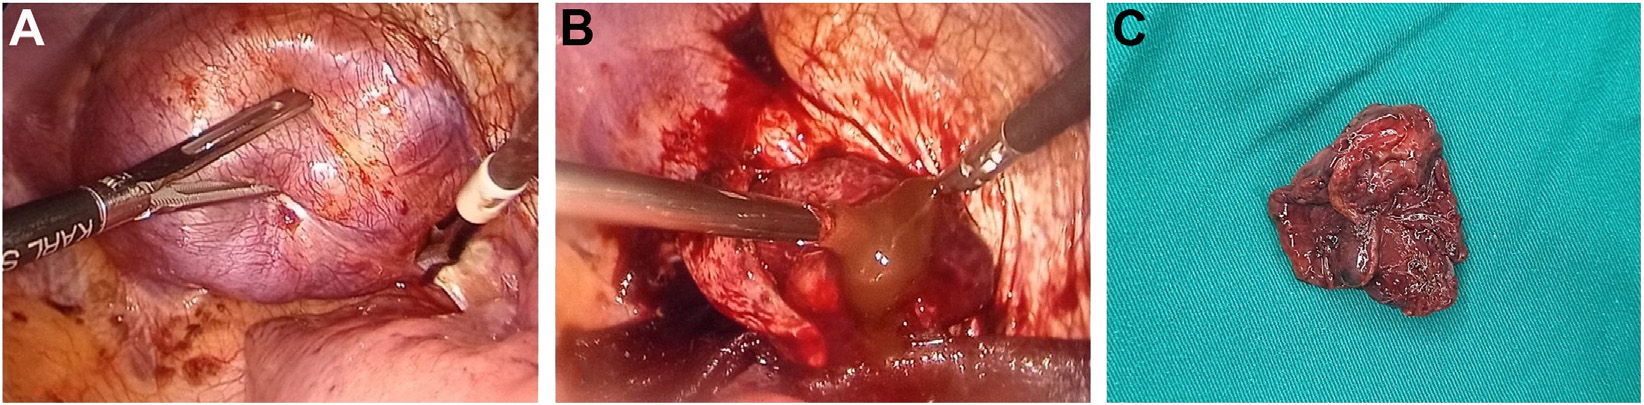

病人接受了全胸腔镜切除手术以切除肿瘤。从胸腔镜看,肿瘤位于横膈纤维肌层下方,向胸腔内突出;肿块大小为6×5×4cm(图3)。

肿瘤具有炎症性质,与周围组织粘连,容易出血

。肿瘤内含有黄褐色粘液;可见分离的前后层。肿瘤被完整切除,并通过内窥镜穿刺器从胸腔中取出。通过连续缝合线恢复横膈膜;放置胸膜引流管

以监测和排出炎性液体。

图3 胸腔镜检查

显示肿瘤位于横膈纤维肌层下方,突入胸腔(A);肿瘤与邻近结构粘连,容易出血,并含有黄褐色粘液(B);横断面显示实性和囊性区域(C)。